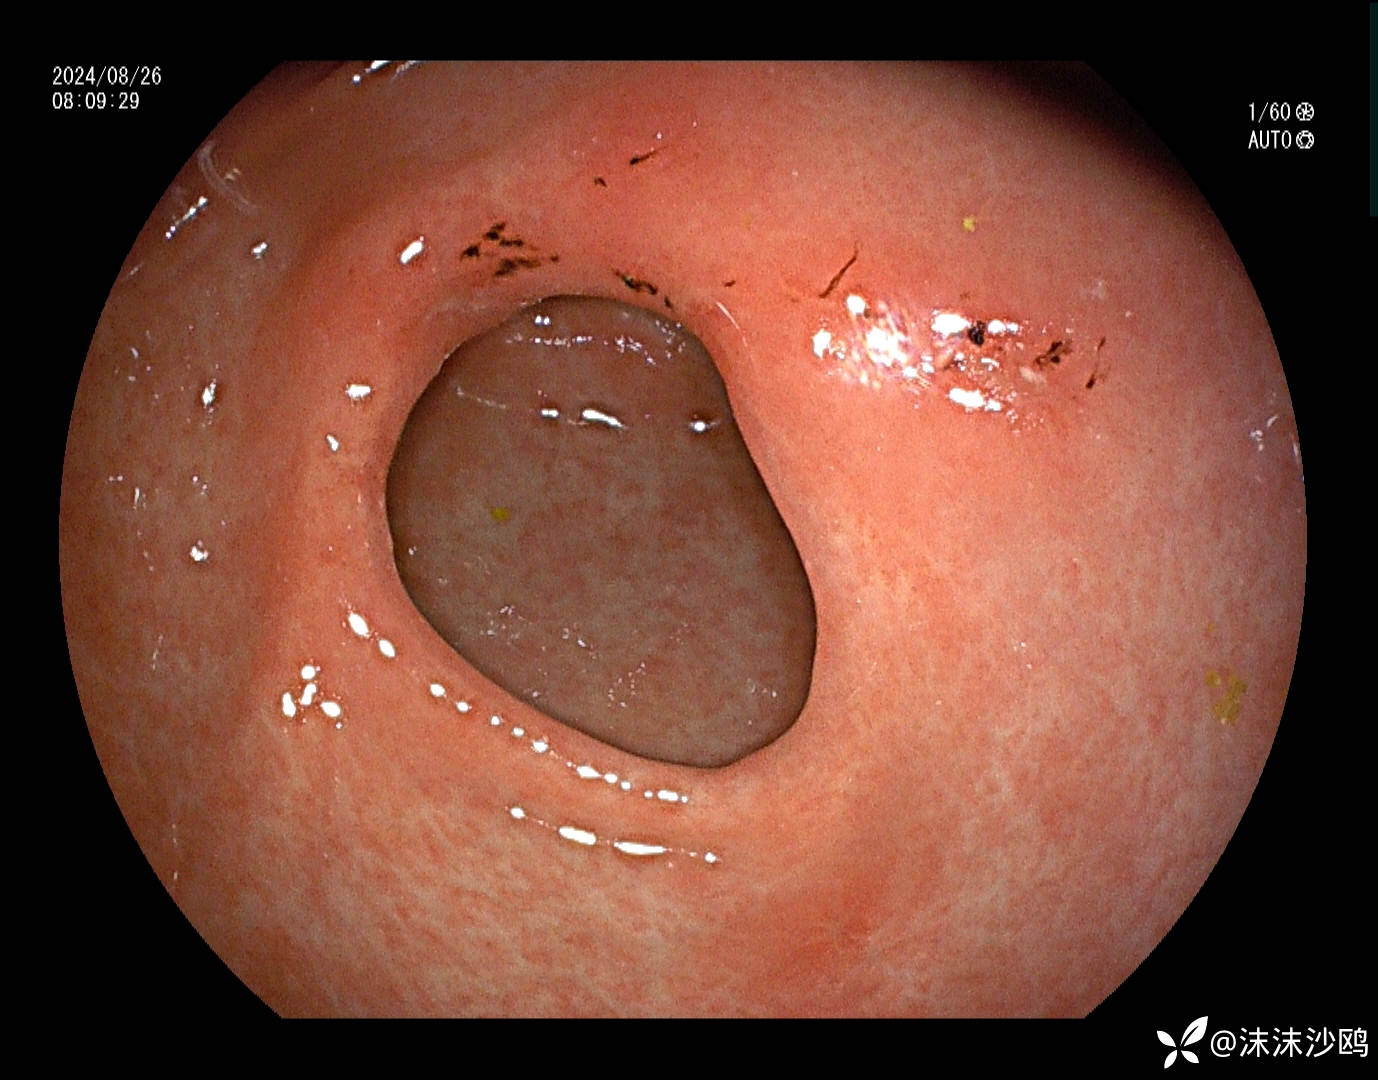

患者男性54岁,因焦虑抑郁在神经内科住院,纳差乏力行普通胃镜检查

中段食管粘膜病变,白色斑块冲洗不掉,且斑块下有粘膜下出血,是药物导致还是感染相关性的食管炎?